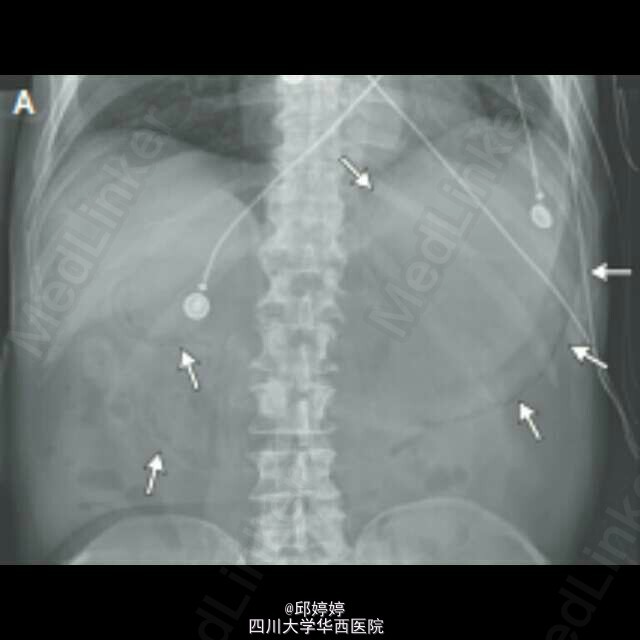

灾难性胃肠积气

患者,老年男性,胰腺癌晚期,腹痛,呕吐12h,触诊腹部压痛,板状腹。平片(图1)示腹腔严重积气,CT(图2-3)示胃肠周围,门静脉积气。患者拒绝治疗,48h后死亡。